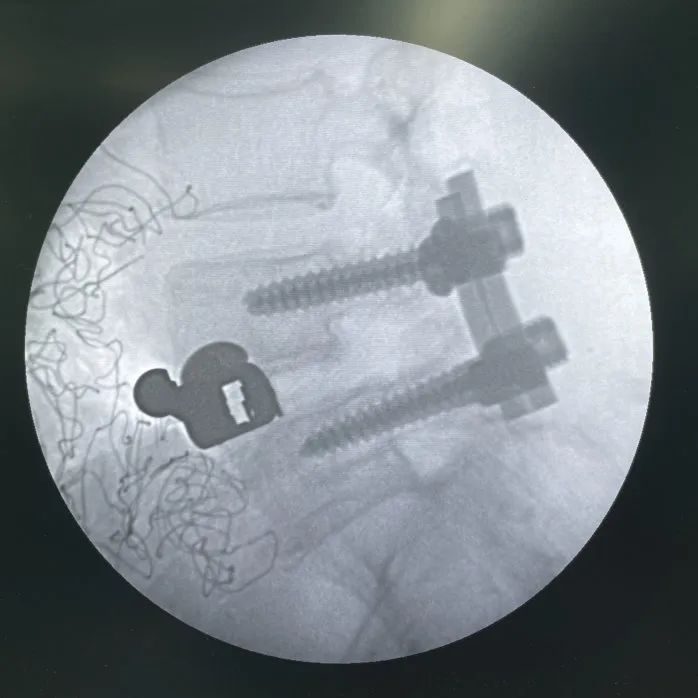

正視圖:頭尾側(cè)固定夾均已完全打入

直視圖:cage與固定夾完全打入后

最終透視